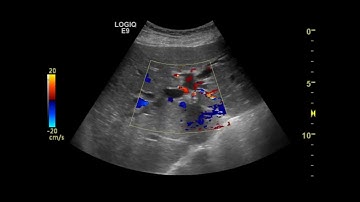

ERCP/SEVERE CHOLANGITIS/MIRRIZI SYNDROME/STENTING DONE